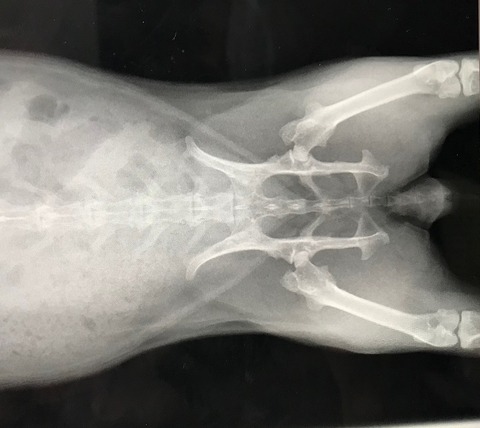

今回は普段の簡易健診にくわえてレントゲンもお願いしました。

ちょっと記憶にあるところで、保護後早々の避妊手術以降、

撮る機会がなかったとちゃうかな、と。

こないだのお腹不調も待合室で食べ始めたから、レントゲンに至らず。

心臓、胸周りほか、腎臓の方とか、一応、何か拾える変化がないか、と…。

所見、特に何って問題は見当たらず、体ん中も準備オーケーでした(。・m・)

レントゲンで見れるよう内臓脂肪もほぼなく健康的